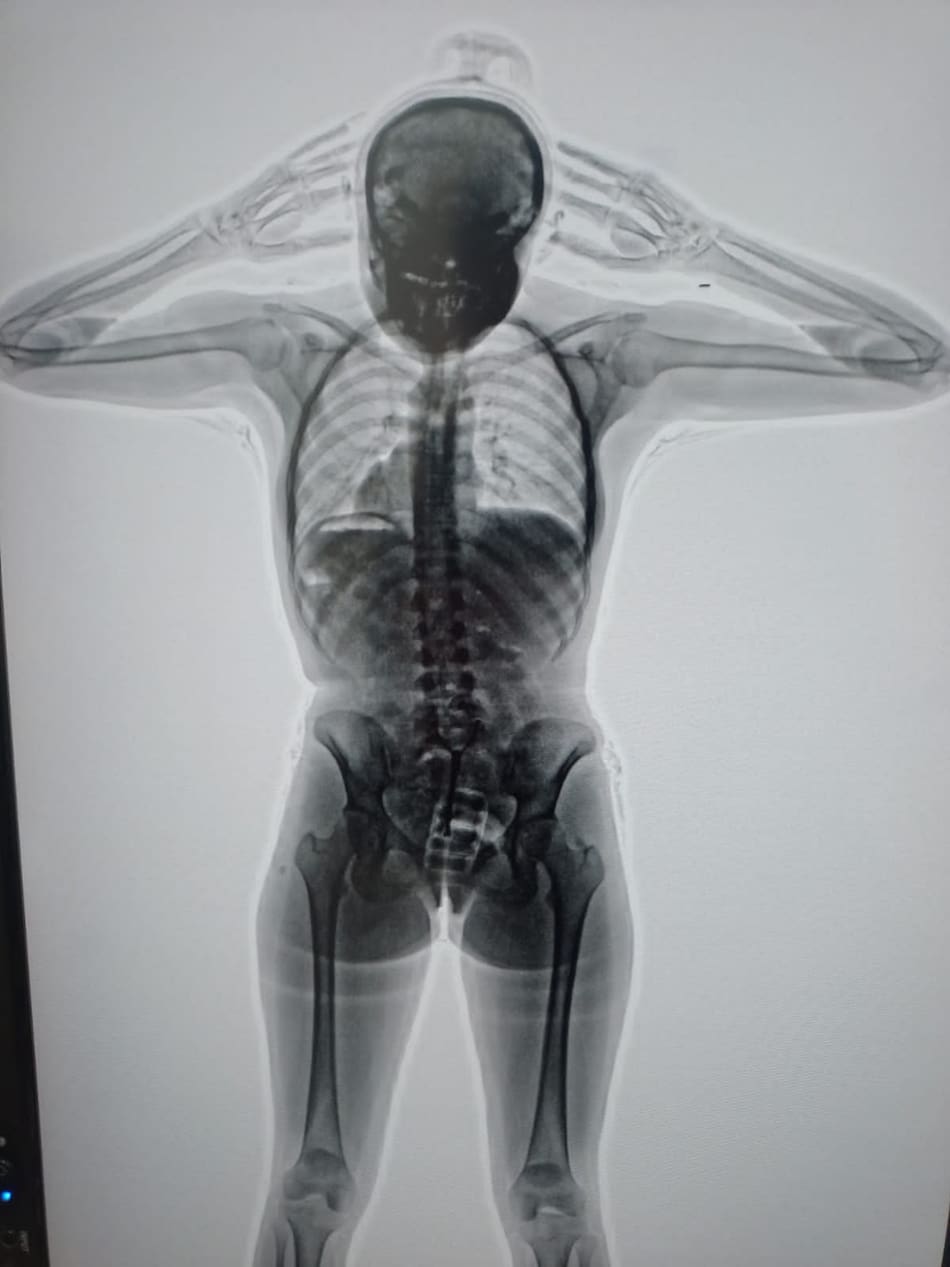

El body scan que detectó la presencia de cocaína en el cuerpo de la detenida. Foto: PSA.

Así, procedieron a una inspección de las pertenencias de la pasajera, que resultó negativa. Sin embargo, sus dudas persistían, por lo cual, con la colaboración de la Policía de Seguridad Aeroportuaria (PSA), procedieron a realizarle un body scan que arrojó imágenes comprometedoras.